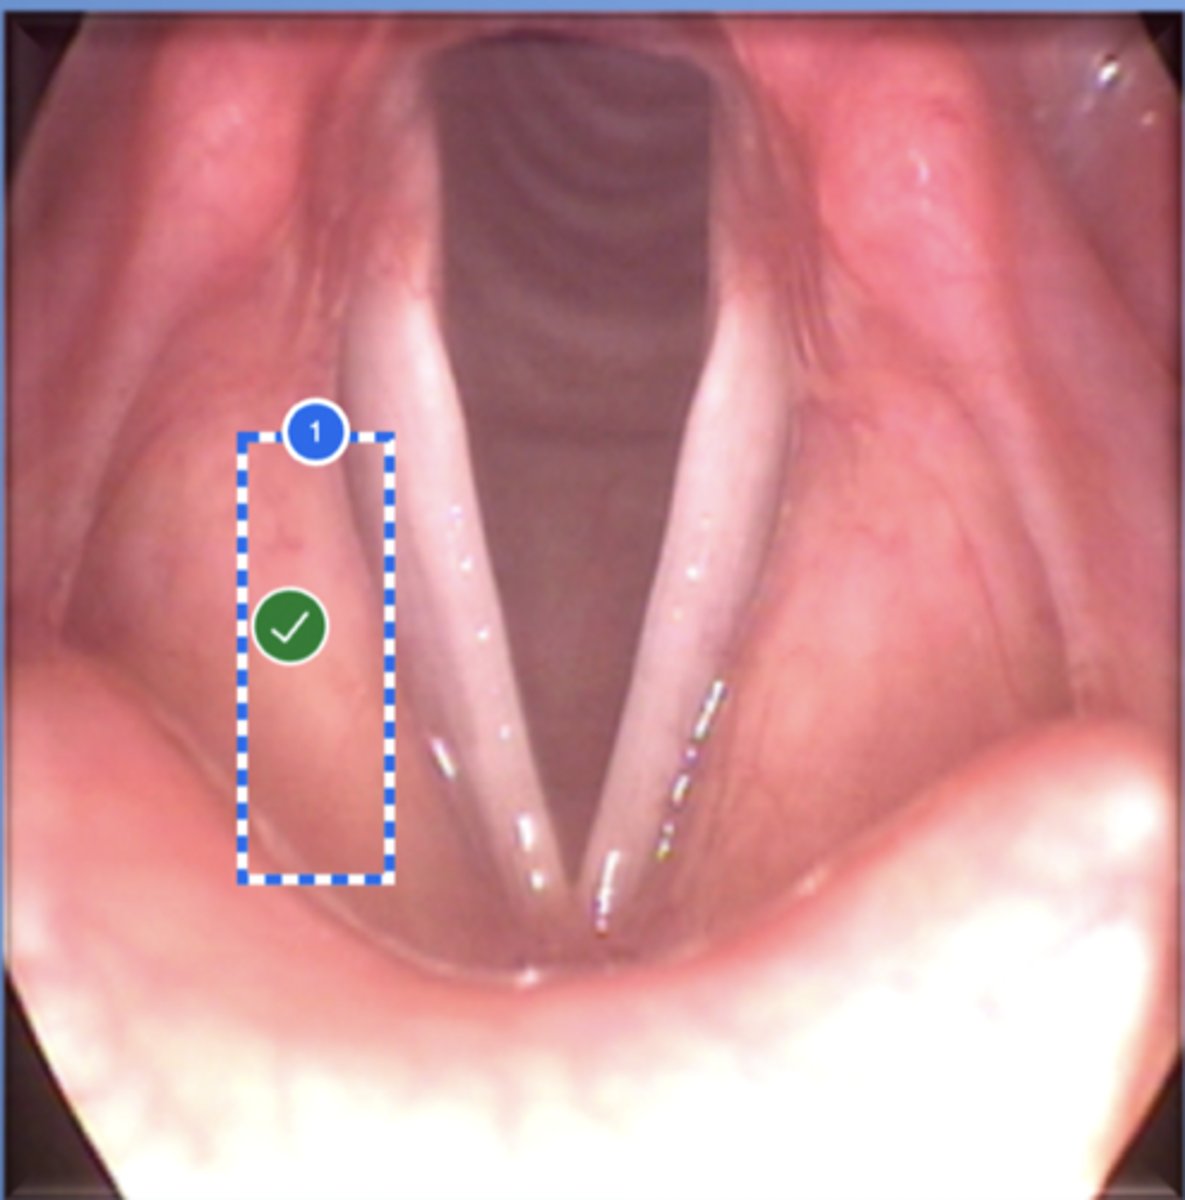

Label left true vocal fold (superior view)

Label right false vocal fold (superior view)

label right arytenoid (superior view)

Label trachea (superior view)

Label epiglottis (superior view)

Label right true vf (superior view)